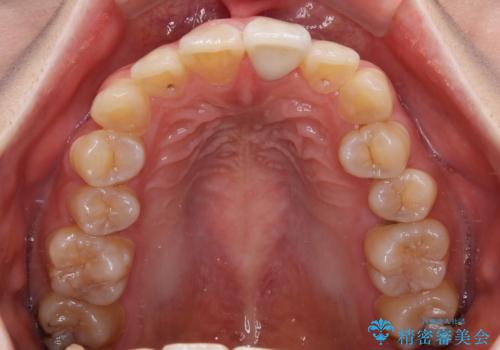

- ぶつけて欠けてしまった前歯を樹脂でつめていたものの、すり減りや変色が顕著とのことで来院された患者様です。

詰め物の詰め直しとオールセラミッククラウンの双方をご提案し、患者様ご希望によりオールセラミッククラウンにて補綴治療を行うこととしました。

歯列全体に表面の着色があったため、クリーニングとホワイトニングを事前に行い、ホワイトニング後1ヶ月ほどおいて、色の落ち着いたところで色合わせを行いました。

本物の歯のような仕上がりとなりました。